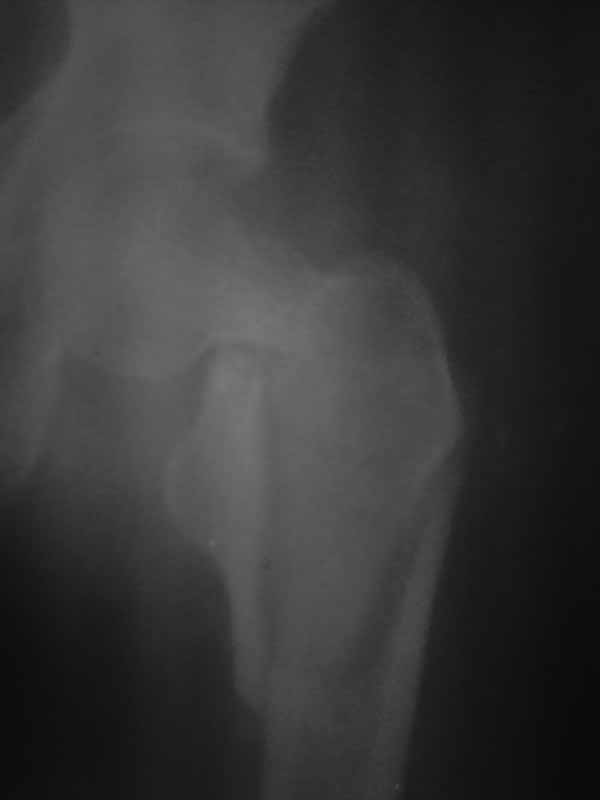

Хотелось услышать дискуссию, по-этому выложил некачественный снимок с вопросом. Стараюсь выложить немного лучше. Гамму она приобрести не сможет. Смущает то что шейка больно хлипкая и винтом развалим ее до конца. На снимке кажется что и фрагмент шейки также сломан вдоль.

Доброго времени суток уважаемые коллеги!! Если бы перелом был чрезвертельным то все примерно было бы понятно. Гамму пациентка не купит, больница тоже ее не купит. Я попытался прислать еще снимки гляньте пожалуйста. Можетбыть вести действительно консервативно чтобы прирос фрагмент межвертельного перелома а потом поднять речь об эндопротезировании, ища квоты?! DXS - я говорю об динамическом бедренном винте с накладкой. Единственно что есть это LSP пластины да в шейку загнать винты АО. А больница наша скоропомощная в г.-герое Москва №68. Спасибо всем ответившим и прочитавшим. Случай не простой.

Нет КТ - качественный Рн нужен. Консервативное лечение здесь не рассматривается, как однозначно калечащее. Видно - нужно быть готовым к открытой репозиции. Винты не обеспечивают достаточной стабильности при такой линии излома. И, даже если бы была возможность ИМ фиксации, я бы предпочёл Динамический Бедренный Винт (так правильно?) в этом случае. Черкните мне, или позвоните, если нужна поддержка, приеду, помогу по соседски-то. Вы же в Коньково? Андрей

Этот случай не является типичным, я бы рассматривал его с точки зрения механики как комбинацию (редкую, надо сказать, комбинацию) латерального и медиального переломов. Если я правильно могу прочитать представленные рентгенограммы, конечно. И нестабильным как раз в данном случае является медиальный компонент повреждения. Поэтому выбор технологии диктуется медиальым, сложным компонентом. Для латерального по большому счёту всё равно - гвоздь или Динамический Бедренный Винт. Для базисцервикальной шейки же гвоздь не даёт особых преимуществ. Репозиция, скорее всего, будет октрытой. Поэтому, DHS в комбинации (если войдёт)с дополнительным антиротационным винтом. Но, -прежде всего, рентгенография нужна приемлемого качества. Так я бы рассуждал, если бы это был наш пациент. С уважением, Андрей